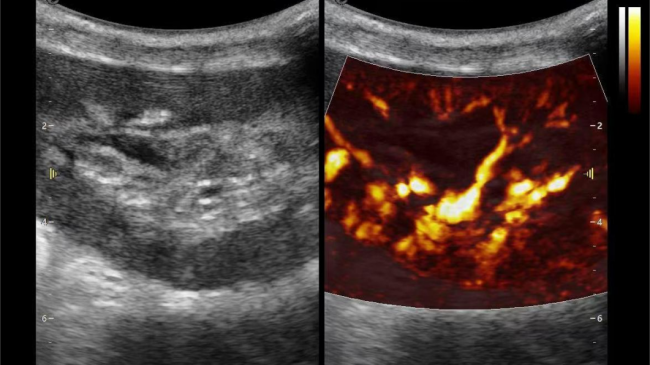

肾脏的灌注评估,RI/VI量化数据

3) 通过血管指数(VI)定量评估局部血管密度,以定量化数据实时监测血流灌注情况,预判肾功能恢复情况;

这一项无创、无辐射操作简便且无需造影剂的黑科技,相当于用"高速摄像机"记录血液细胞的运动轨迹,让血管并发症"无处遁形。

从术前评估到术中到术后,再到终身监护,当20-50μm级的超微血流信号在屏幕上跳动,我们看到的不仅是技术的精进,更是生命的律动。iPlane Vascular正在重新定义肾移植监护的标准——让医生拥有了"显微视力",让每一个微小血管的异常都无所遁形,让每一次免疫排斥的萌芽都被及时扼制。